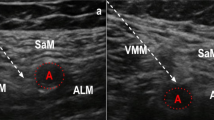

Ultrasound-guided selective tibial nerve block (A1-2) and popliteal plexus block. (B1–2). Tibial nerve block: The subjects were supine with participants’ legs bent upwards to 90 degrees. (A1) We fitted the ultrasound transducer position in the short-axis view of the tibial nerve on the posterior thigh. We placed a block needle (cyan arrows) from the lateral side of the thigh to the medial side of the tibial nerve. (A2) Local anesthetics were injected around the tibial nerve component. Popliteal nerve block: The subjects were supine, with the knee slightly flexed. (B1) We positioned the ultrasound transducer in the short-axis view of the femoral artery, which entered the popliteal fossa. We pierced the nerve block needle (cyan arrows) into the vastus medialis muscle. The target of the needle tip was the posteromedial side of the femoral artery. (B2) Local anesthetics were injected between the sartorius and the adductor magnus muscle, spreading into the popliteal fossa’s direction. TN, Tibial nerve; CPN, common peroneal nerve; BFM, biceps femoris muscle; STM, semitendinous muscle; FA, femoral artery; SM, sartorius muscle; AMM, adductor magnus muscle; VMM, vastus medialis muscle; White asterisk, local anesthetics.

For the PPB procedure, the subject remained supine with the knee slightly flexed (Fig. 4_B1). The ultrasound probe was positioned at the same level as the ACB and moved downward along the femoral artery until the artery separated from the sartorius muscle at the distal end of the adductor canal, resulting in the adductor hiatus7. We identified the target site as the space between the vastus medialis and adductor magnus muscles, with slight posteromedial encroachment of the sartorius muscle. The needle was inserted through the vastus medialis muscle and positioned to approach the artery tangentially in the medial artery region (Fig. 4_B2). We then administered 10 mL of levobupivacaine 0.25% to allow for distribution between the artery and the adductor magnus muscle.